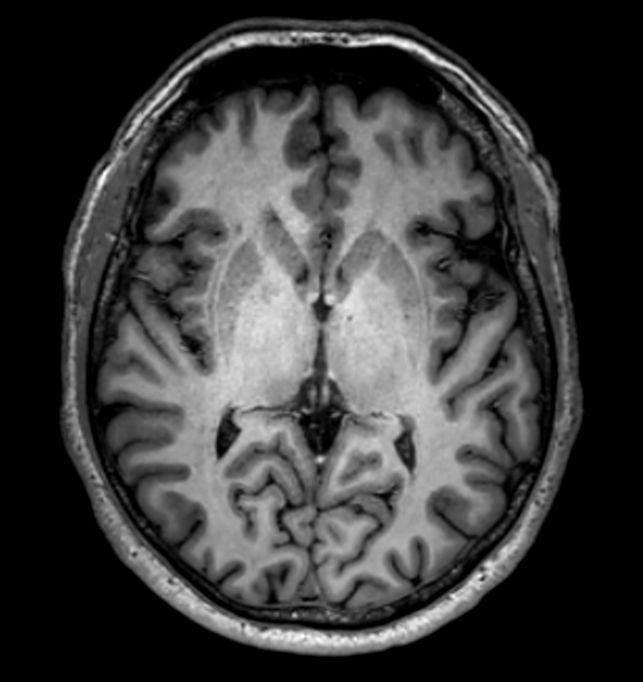

3D VIEW - T1w TSE (axial reformat)